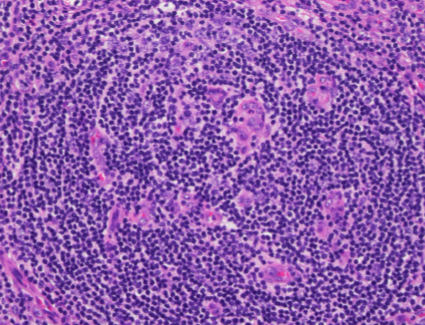

H&E (400x magnification)

The low power view shows lymph node tissue with abnormal follicles, including partial hyalinization, regression of germinal centers, and concentric mantle zone lymphocytes showing "onion skinning" appearance. Several follicles show prominent penetrating venules. No Hodgkin-Reed-Sternberg cells or LP cells were identified.